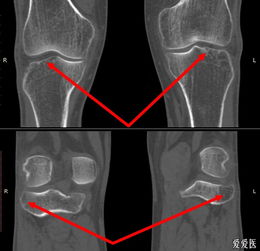

胫骨平台是位于胫骨上端的一个平台,与股骨的髁部形成膝关节。胫骨平台骨折是指胫骨平台部位发生的骨折,可能是由于直接撞击、跌倒或扭伤等原因引起。根据骨折的严重程度和位置,可分为多种类型,如单纯骨折、粉碎性骨折等。

胫骨平台关节面塌陷小于2mm